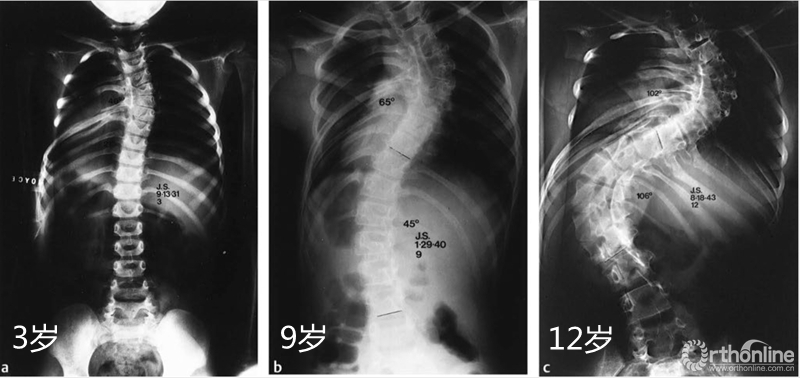

图2: 3岁女孩先天性脊柱侧凸,侧凸角度40°,未接受任何治疗;B:该患者到9岁时,侧凸角度进展到65°,并且出现下方胸腰段出现45°的代偿性侧弯;C:12岁时胸弯的角度进展到102°,胸腰弯进展到106°。(Congenital deformities of the spine by Robert B. Winter, Thieme Stratton, New York, 1983)